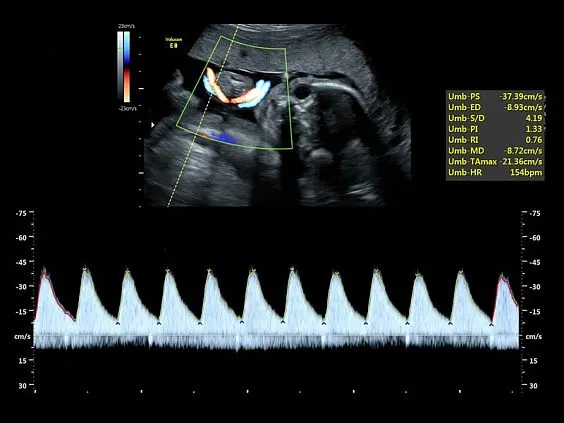

Клинические изображения

- Тканевой допплер.

- Высокочувствительный допплер (HD-Flow).

- Постоянно-волновой допплер (CWD).

- Высокочувствительный допплер (HD-Flow).

- Постоянно-волновой допплер (CWD).

- Advanced STIC — расширенный программный пакет для исследования сердца плода в режиме 4D для объемных датчиков:

- Использование цветного, энергетического допплера, В Flow — режим STIC.

- Сочетание с М-режимом — STIC-M-Mode.

Главное достоинство Voluson E8 — качество изображения. Система обеспечивает превосходную чёткость и контрастность как в двухмерном, так и в трёхмерном и четырёхмерном форматах. Она оснащена современными допплеровскими режимами для анализа кровотока и передовыми инструментами трёхмерной реконструкции. Встроенные интеллектуальные алгоритмы автоматизируют многие процессы, что позволяет врачу работать быстрее и точнее.

HDlive Flow и Flow Silhouette помогают детально визуализировать сосудистую сеть и анатомические особенности кровотока.